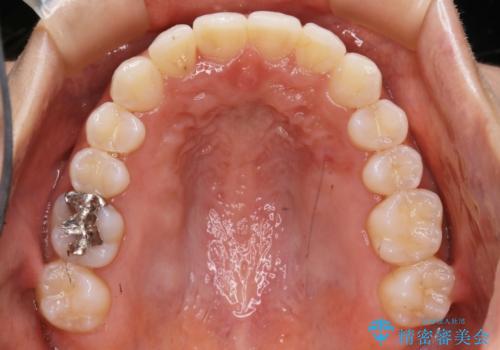

【非抜歯】下の前歯が1本少ない場合の矯正治療

- 前歯のガタつきを主訴に来院されました。

生まれつき下の前歯が1本少なく、その分のスペースを上の前歯がガタつくことで埋めているという状況でした。

上下それぞれのガタつきをとっていく過程で、歯1本分のスペースの差を、上顎の前歯のIPRで調整して並べる方法をご提案させていただきました。